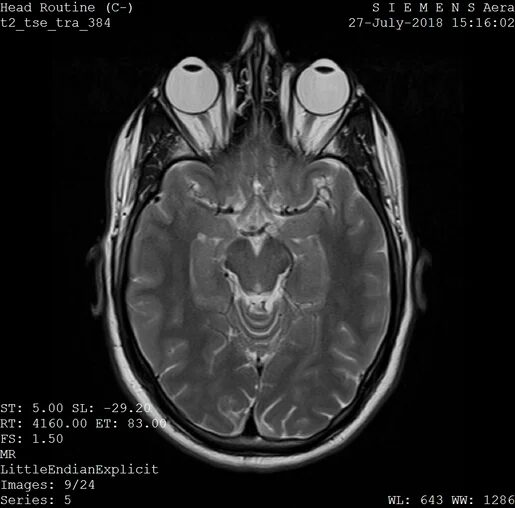

Many people are starting to use AI chatbots, like ChatGPT from OpenAI and Gemini from Google, to ask questions about their health and get advice on medical issues. Some folks even use questionable apps that claim to check if someone’s genitals are free from disease using AI. Recently, users on the social media platform X (formerly known as Twitter) have been encouraged to upload their X-rays, MRIs, and PET scans to an AI chatbot called Grok to help interpret these medical images.

Elon Musk, the owner of X, has encouraged users to upload their medical images to Grok, admitting that the AI’s results are still in the early stages but claiming that it will improve over time. The idea is that by submitting medical images, users can help the AI become better at interpreting scans accurately. However, it’s unclear who will have access to the data collected by Grok. According to Grok’s privacy policy, X shares some user information with a number of “related” companies, but it doesn’t specify who those companies are.